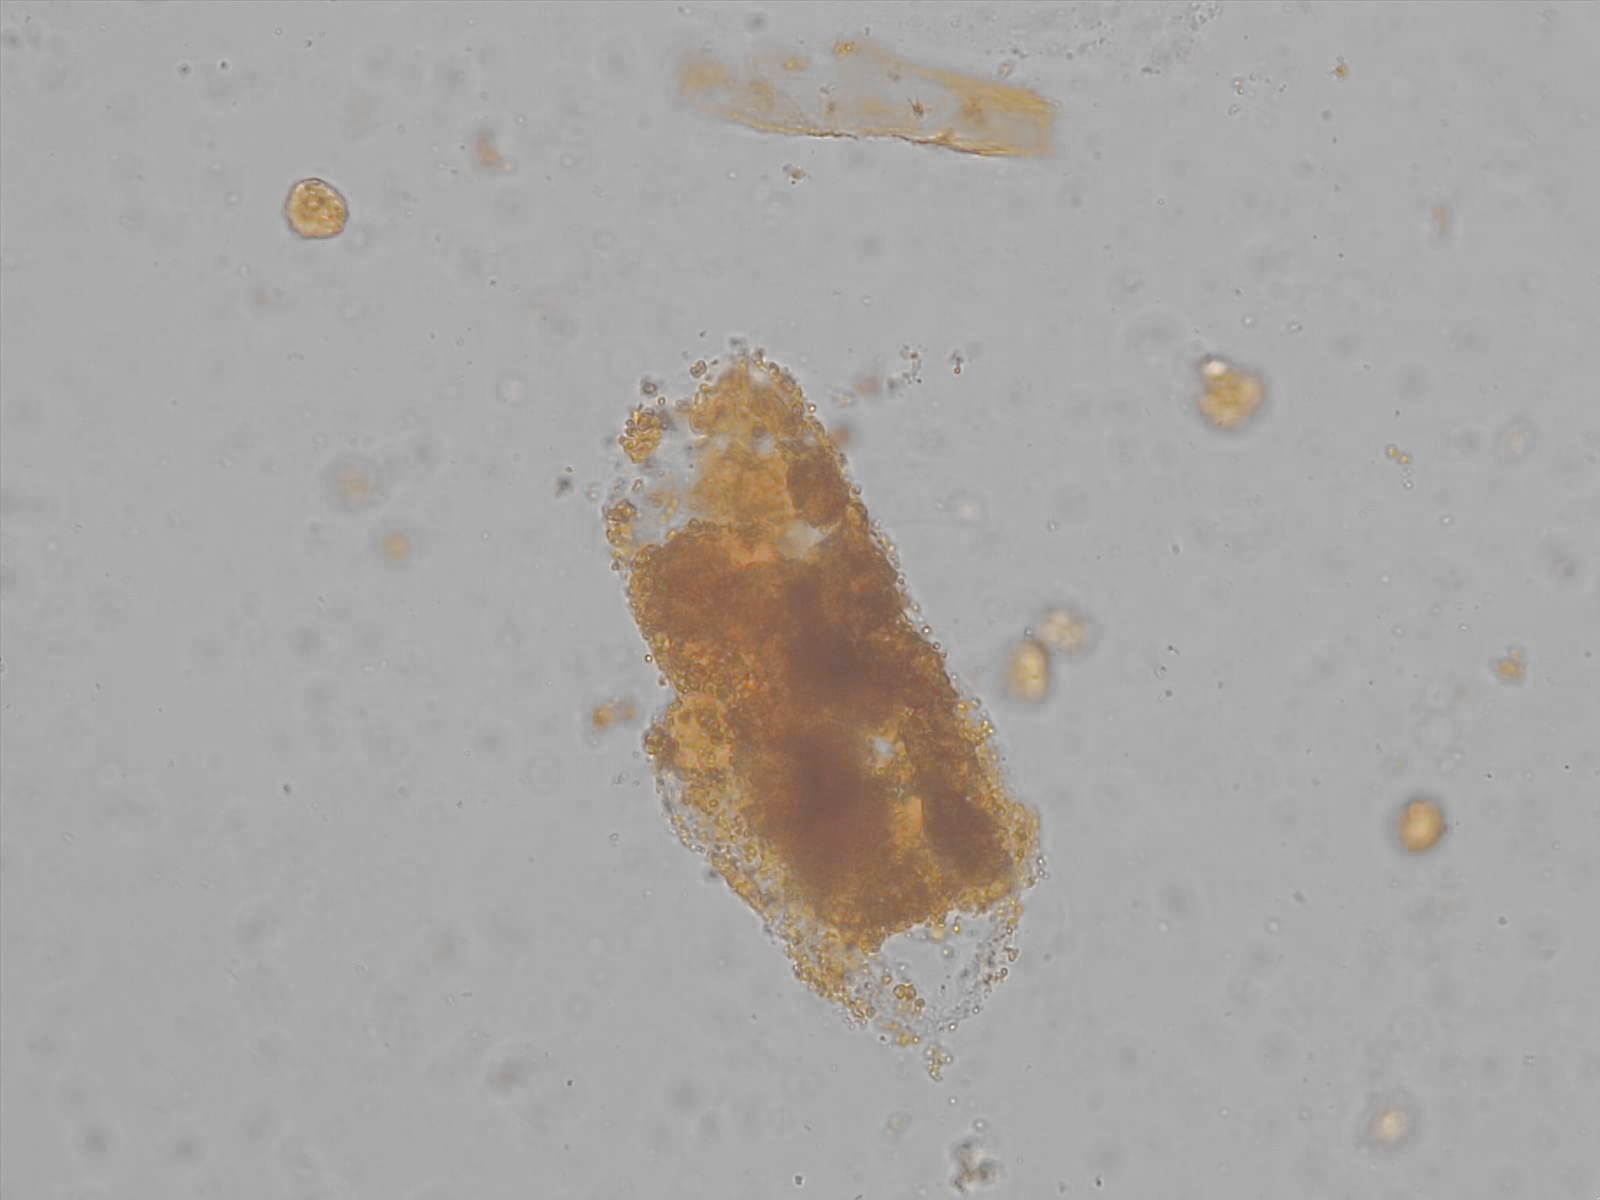

Bilirubin cast

Bilirubin casts (as well as bilirubin crystals) are formed by precipitation and adsorption of conjugated bilirubin in the renal tubules, with existing casts – such as hyaline, wax, granule or fat casts – becoming yellow discolored. They can contribute to tubular damage via direct toxicity on tubulus epithelial cells and by mechanical obstruction of the tubulus lumen. This mechanism is referred to as "bile cast nephropathy," a form of acute renal insufficiency that occurs in patients with liver disease or obstructive icterus.